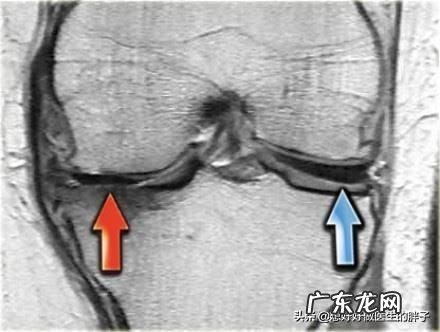

diyi,半月板撕裂 。我们膝关节内有两块非常重要的软骨,因为形状像月牙,所以称之为半月板 。半月板其实就是两块比较大的软骨,在关节的屈伸活动当中,它的形态是动态变化的,会有厚薄的变化以及宽窄的变化,这样才能更好的缓冲关节在运动当中承受的压力,匹配关节的形状,使关节能够做正常的屈伸运动 。